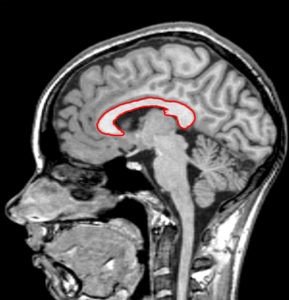

Мозолистое тело головного мозга

Гипоплазия мозолистого тела головного мозга у ребенка является опаснейшим заболеванием, заключающееся в отсутствии мозолистого тела ─ отдела, в котором происходит скопления нервных волокон, осуществляющих нейронное взаимодействие между правым и левым полушариями головного мозга. Это заболевание не является приобретённым, а только врождённым. Оно диагностируется как во внутриутробном периоде развития, так и в течение 2 лет с момента рождения. В 70–75% случаях недоразвитость мозолистого тела у ребёнка приводит к инвалидности, шизофрении и судорожным припадкам. Причины заболевания до сих пор не выяснены, но к неблагоприятным факторам относят интоксикацию будущей мамы во время беременности.